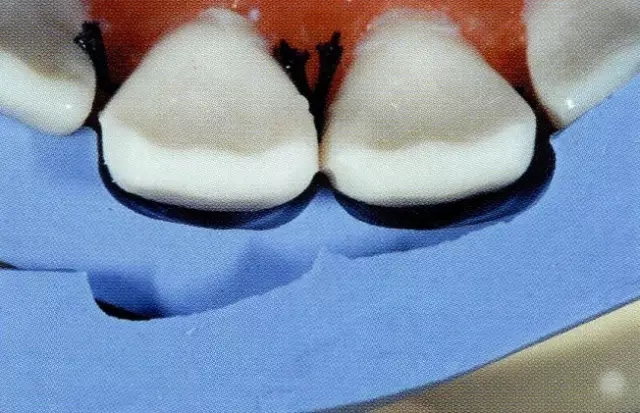

圖1 失敗的牙體預(yù)備。用硅橡膠模型確認(rèn),得出右上1的唇側(cè)打磨量過多。

另外,貼面也是不是日常臨床中經(jīng)??梢宰龅?,它也與全覆蓋冠和嵌體等不同,所以牙體預(yù)備上很多處理都讓人丈二和尚摸不著頭腦。想必這個(gè)很多醫(yī)生都經(jīng)歷過,在修整預(yù)備好的牙體時(shí)會有制備過度的問題。(圖1)

重要的是要事先腦海里擁有預(yù)備牙體形態(tài)。應(yīng)用硅橡膠印??梢源_認(rèn)牙體預(yù)備的深度,其原則就是打磨就停留在牙釉層。